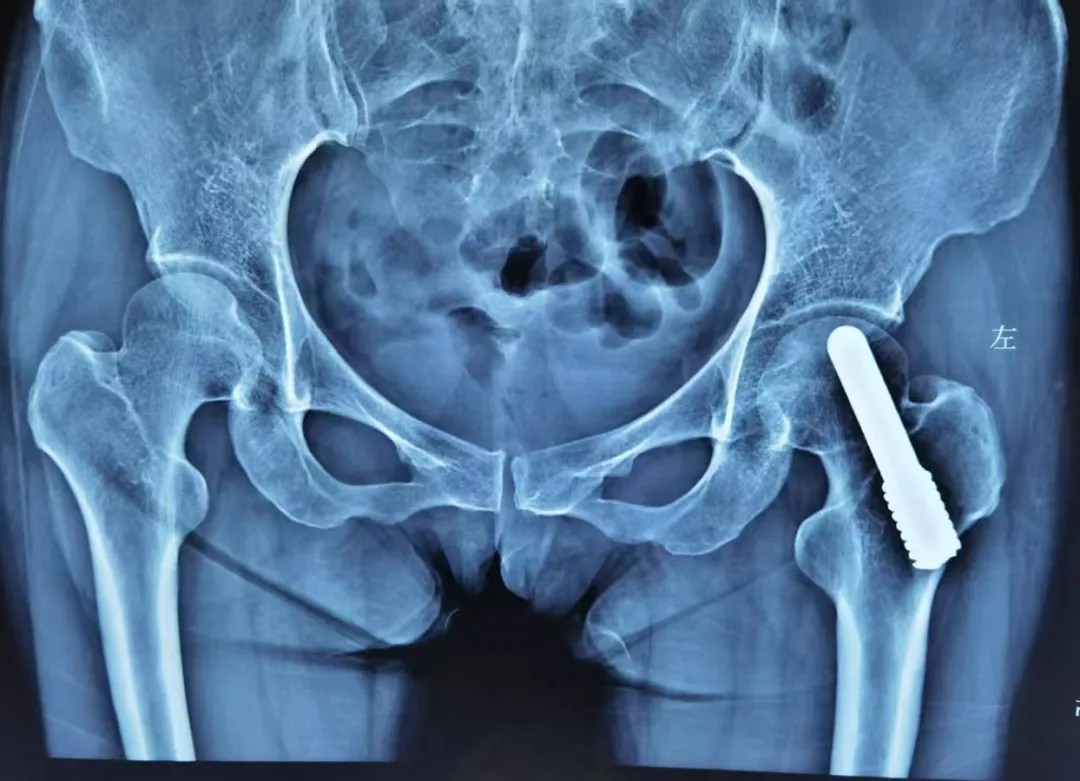

晚期:換髋昰(shi) “最優(you)解”

股骨頭壞死晚期,此時股骨頭完全塌陷,保留股骨頭也(ye)沒有(yǒu)意義了(le)。此時多(duo)采取人(ren)工(gong)髋關節(jie)置換術(shù),能(néng)快速(su)緩解疼痛、恢複活動(dòng)能(néng)力(li),目(mu)前(qian)手術(shù)技(ji)術(shù)成(cheng)熟,假體(ti)壽命可(kě)達20年(nian)左右。